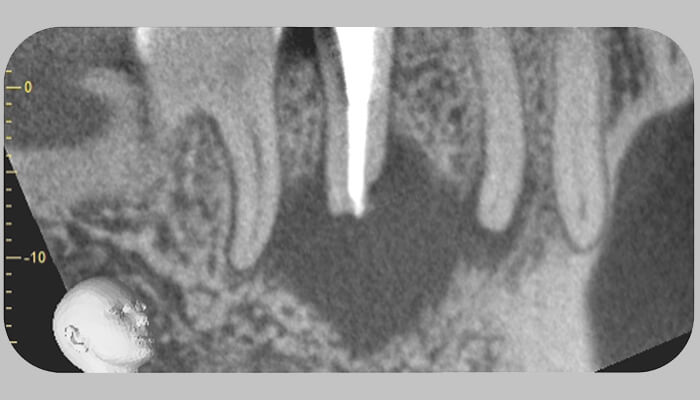

2. エックス線検査とコーンビームCT検査を行いました。

3. 過去に外傷の既往がある歯だったようで、右上1のみ歯髄腔の病的な狭窄をみとめました。

4. 相談の結果、通法の根管治療でのアプローチは難しいと判断し、外科的根管治療(歯根端切除+逆根管充填)で対応することになりました。

3. コーンビームCTで病変の範囲の精査をしました。右下6,4の根尖まで骨欠損は広がっていましたが、生活反応が見られたため原因は右下5と判断し、まず根管治療で対応しました。

5. 術後1年ほど経過し、また痛みが再発しました。コーンビームCTを撮影すると病変の範囲はあまり変化が見られないため、外科的根管治療を行うことになりました。

2. エックス線とコーンビームCTで検査したところ、根尖部で根管は病的な狭窄を認めました。

2. コーンビームCT撮像を行ったところ口蓋根、遠心頬側根に関して、根尖部と根周囲の骨欠損像は確認できず、問題は近心頬側根に限局していました。

近心頬側根について、根尖まで処置されている第一根管と、根の半分程度まで処置されている第二根管が確認でき、第一根管からは溢出した不透過性材料の存在を認めました。

根尖部では、頬側皮質骨は開窓しておらず骨欠損像は根尖から遠心方向に進展しています。